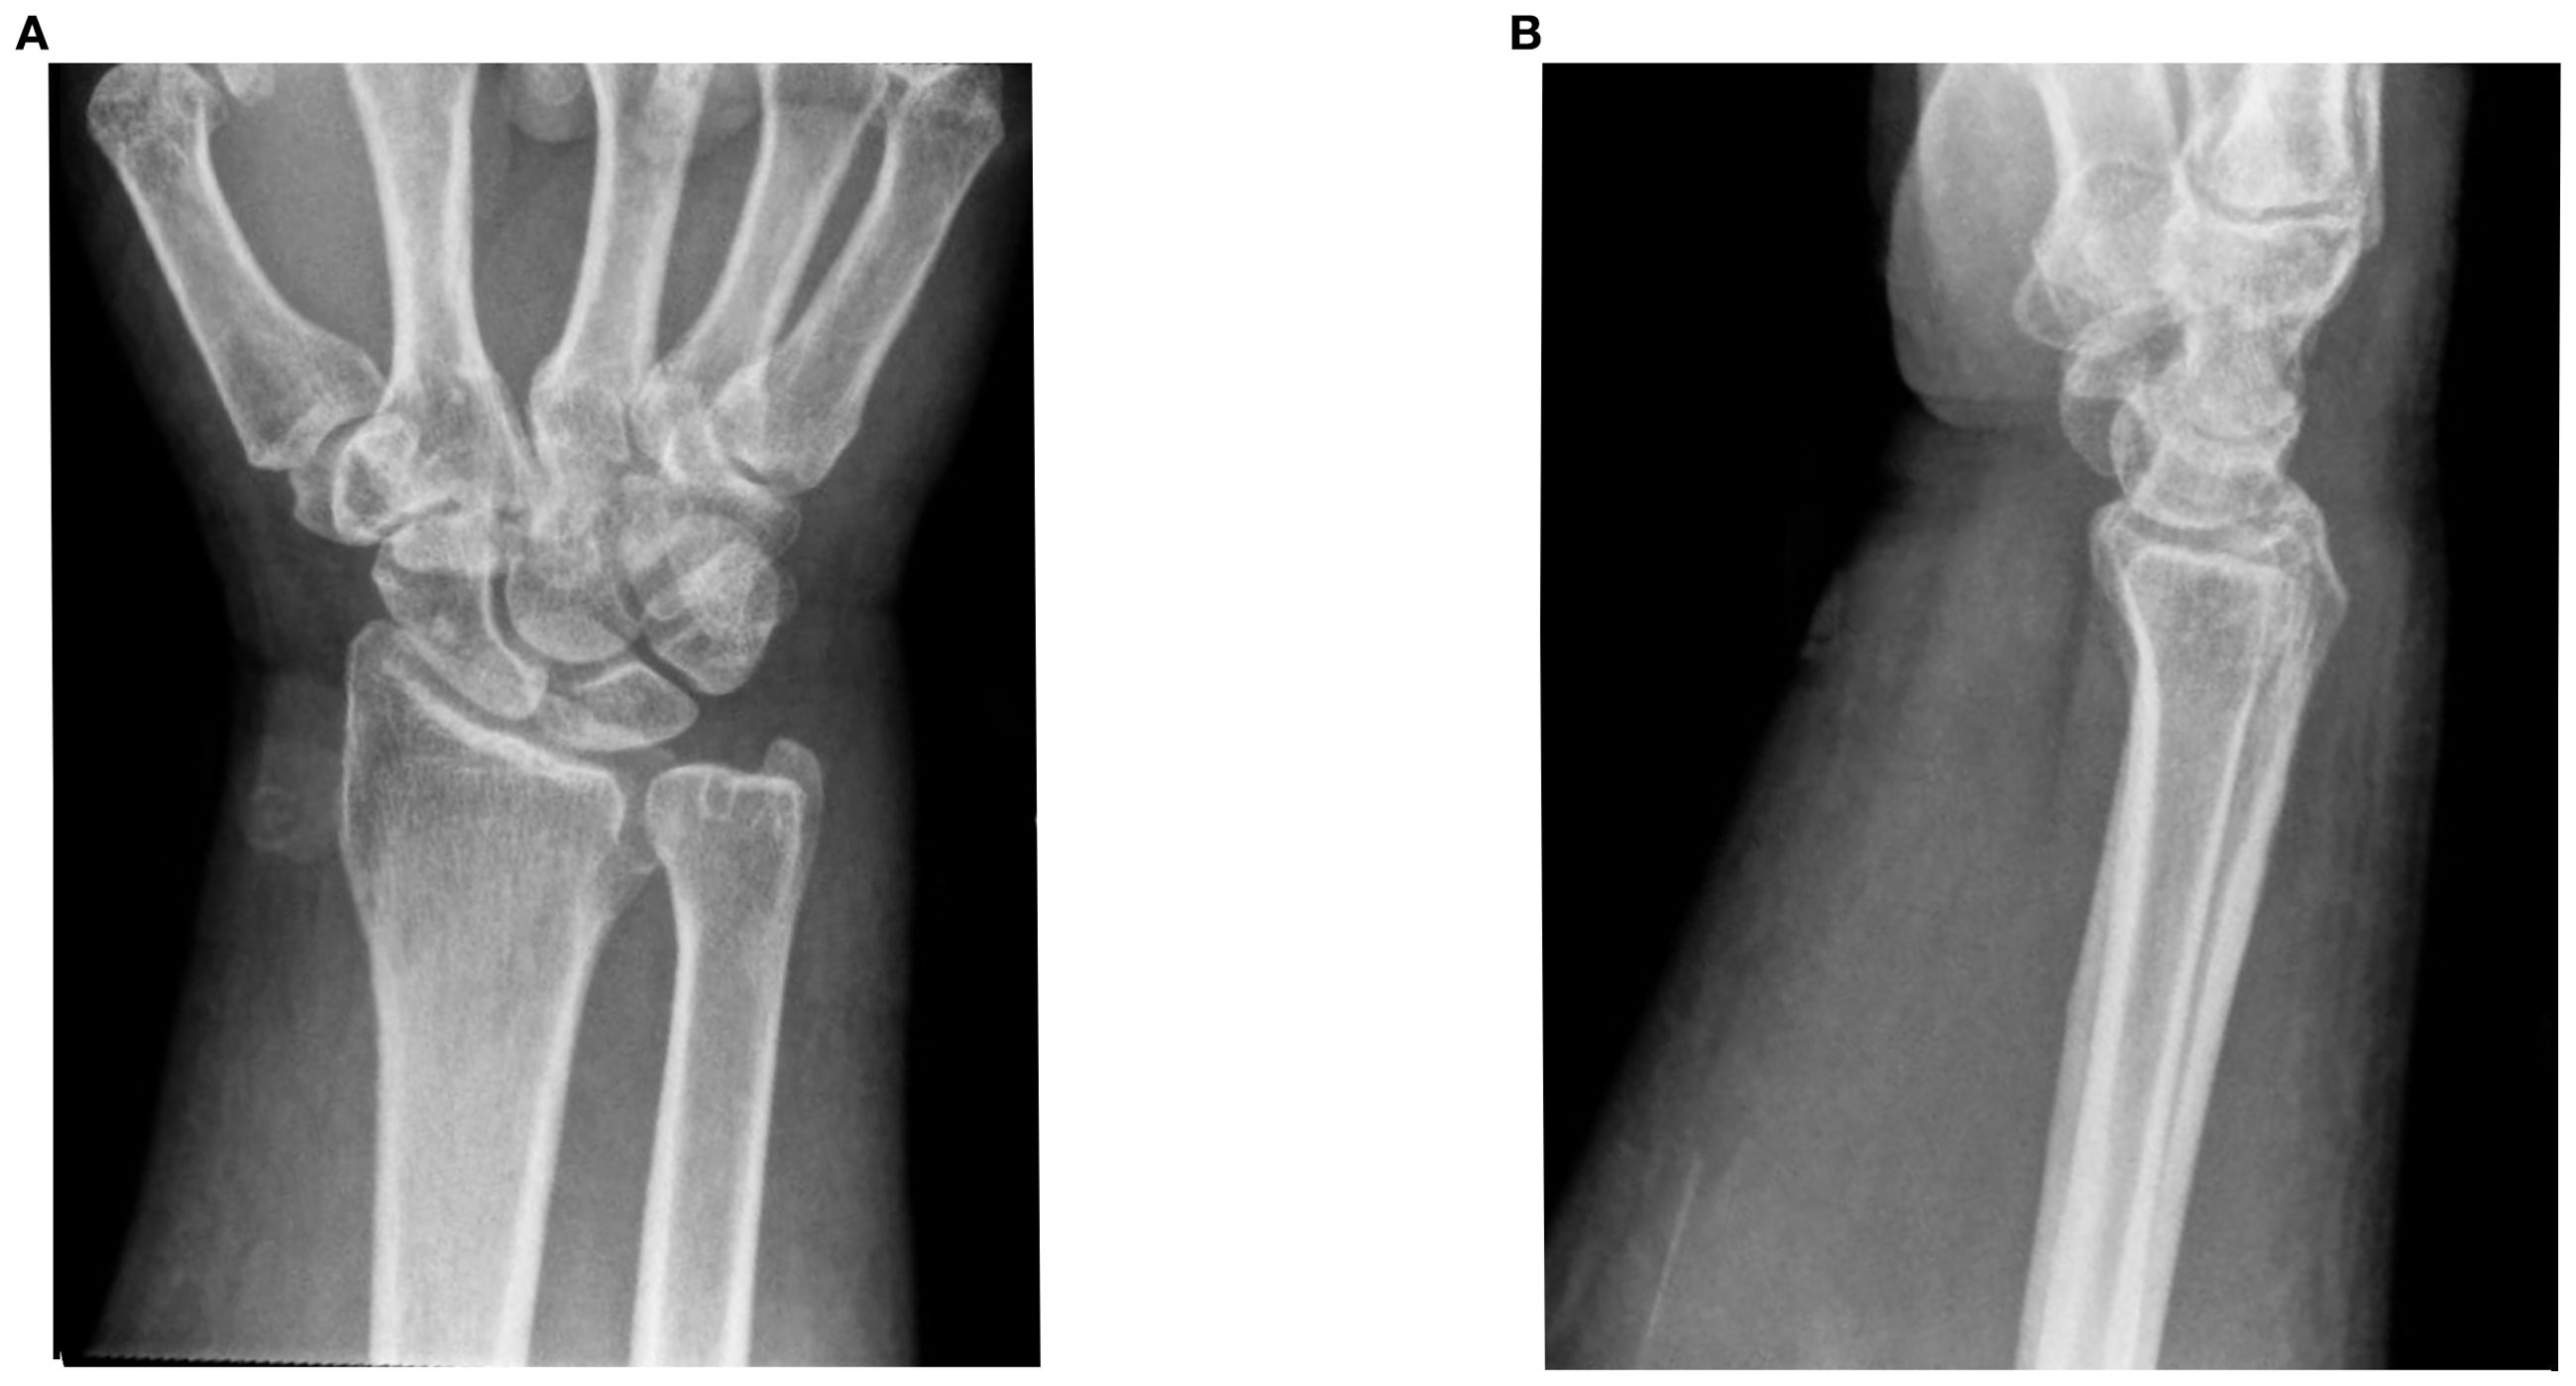

He was started on ipilimumab (91mg)/nivolumab (274mg). He completed 4 cycles (9 weeks) with partial response. He developed grade 2 colitis (per Common Terminology Criteria for Adverse Events [CTCAE], version 5) (3) after the 4 treatment cycles and was switched to nivolumab alone (480 mg). He was treated with a prolonged budesonide taper (entailing 9 mg daily for 2 weeks, then 6 mg daily for 2 weeks, then alternation between 6 mg and 3 mg daily for 2 weeks, then 3 mg daily for 2 weeks, then alternation between 3 mg and 0 mg daily for 2 weeks). This was followed by a prednisone taper (entailing 5 mg daily for 2 weeks, then 2.5 mg daily for 2 weeks). He continued immunotherapy until cycle 7 (33 weeks) after which he developed symptoms of diffuse myalgias, joint stiffness, and fatigue. The CK level obtained at that time was normal (161 U/L). He became unable to perform his activities of daily living requiring hospital admission within that month. This was approximately 5 days after completing the prednisone taper and 8 months after starting nivolumab alone. His labs were notable for white blood cell count (WBC) (15.9 K/uL), C-reactive protein (26 mg/L), elevated transaminases (aspartate aminotransferase [AST], 99 U/L and alanine aminotransferase [ALT], 102 U/L), and normal CK (202 U/L), all of which were collected around 101 days from when budesonide was started. The autoimmune workup including rheumatoid arthritis (RA), and systemic lupus erythematosus (SLE) was negative (Table 1). Viral causes tested included hepatitis C which was negative. A right wrist x-ray was obtained for further evaluation of severe wrist pain and stiffness which showed diffuse soft tissue swelling (Figure 1). Initially, symptoms were thought to be due to osteoarthritis. He was discharged with prednisone 20mg daily for 7 days, which was tapered to 5mg daily over 3 weeks. The aldolase level (which was collected approximately 103 days from when the budesonide course was started) was found to be elevated at 23.7 U/L (reference range: < 7.7 U/L). He was diagnosed with grade 2 myositis (Figure 2) (3). Grade was determined according to the CTCAE v.5 which was based on severity of symptoms and interference with activities of daily living (3). Muscle MRIs and electromyograms (EMG) were not performed. A muscle biopsy was not completed since the patient already received steroid treatment with budesonide. Given improvement in symptoms, he was continued on the steroid regimen and tolerated it well. At his 2-week follow-up visit, his myalgia had improved. His aldolase level gradually declined back to normal (7.1 U/L) over the following 5 months. Immunotherapy was discontinued given 2 irAEs. Staging scans that were obtained after discontinuing immunotherapy revealed partial response. The patient remains off treatment and on surveillance.

Figure 2. Timeline of event. (A) Case 1. (B) Case 2. Figure illustrating timeline of major events including diagnosis, treatment, laboratory parameter for the 2 cases. CK, creatine kinase.

At his 1-week follow-up visit, while on the maintenance dose, his muscle pain and stiffness worsened. Unsure if his endocrinopathy was worsening or if he was not receiving the correct treatment, further blood work was completed. He had a normal CK level (68 U/L), so myositis was ruled out. Despite myositis being ruled out, he was hospitalized again for persistent symptoms. This was approximately 10 weeks after starting ipilimumab/nivolumab. At that time, his labs were notable for a normal CK (158 U/L) and elevated transaminases (AST, 49 U/L and ALT, 91 U/L). His autoimmune workup including RA, SLE was negative otherwise (Table 1). Hepatitis C was negative. He was ultimately discharged with methylprednisolone (1mg/kg) for debilitating pain attributed to an unknown autoimmune/inflammatory syndrome from immunotherapy treatment. This was tapered over the next 6 weeks back to his prior maintenance dose. During his admission, a muscle biopsy was not completed as he had already received steroid treatment for his hypophysitis. Additionally, muscle MRIs and EMGs were not performed. He was seen at a follow-up visit 3 weeks after discharge. His aldolase level was checked (which was approximately 24 days from when methylprednisolone was started) and was elevated (9.6 U/L). His CK level remained normal (110 U/L). He was diagnosed with grade 3 myositis (Figure 2) (3). He continued the methylprednisolone taper since it was well-tolerated and resumed his maintenance hydrocortisone dose around 3 weeks later. At follow-up visit that week, he had improvement in myalgias. His aldolase level normalized to 3.7 U/L over the following 6 months. Immunotherapy was discontinued given 2 irAEs requiring hospitalization. He remains on surveillance with no evidence of active disease on staging scans.

Studies have shown that patients in the acute setting of glucocorticoid-induced myopathy can have high aldolase levels with improvement within 3-4 weeks of discontinuing or reducing the steroid dose (12–14). This is typically seen at doses exceeding 60mg prednisolone daily (or equivalent) (12–14). Chronic steroid myopathy, however, is typically seen with steroid use for more than 4 weeks and in doses exceeding 10mg prednisolone daily (or equivalent) (12–14). In the setting of chronic steroid myopathy, aldolase levels have been shown to be typically normal (13). In the setting of inflammatory myopathies, or in our case of ICI-myositis, and prior steroid exposure, it becomes challenging to distinguish whether the aldolase elevation is due to the underlying disease or muscle damage related to the steroid. Studies have shown that EMG or muscle biopsy findings can aid in distinguishing between the two pathologies, however, these additional tests were not completed among our patients (13). Therefore, our study findings suggest that aldolase elevation may be a sensitive marker for ICI-myositis in the setting of prior steroid exposure. It is important to note, however, that for Case 1, he was started on steroids (with budesonide) over 10 weeks in advance from when aldolase was measured and tapered (Figure 2, box A). In this setting of chronic steroid use, we would expect to see normal aldolase levels. Additionally, after the completion of the steroid course (Case 1) or taper down to the maintenance dose (for adrenal insufficiency in Case 2), the aldolase level remained elevated for over 20 weeks which is atypical for steroid-induced myopathy, although further tests such as EMGs and muscle biopsies are needed to confirm.